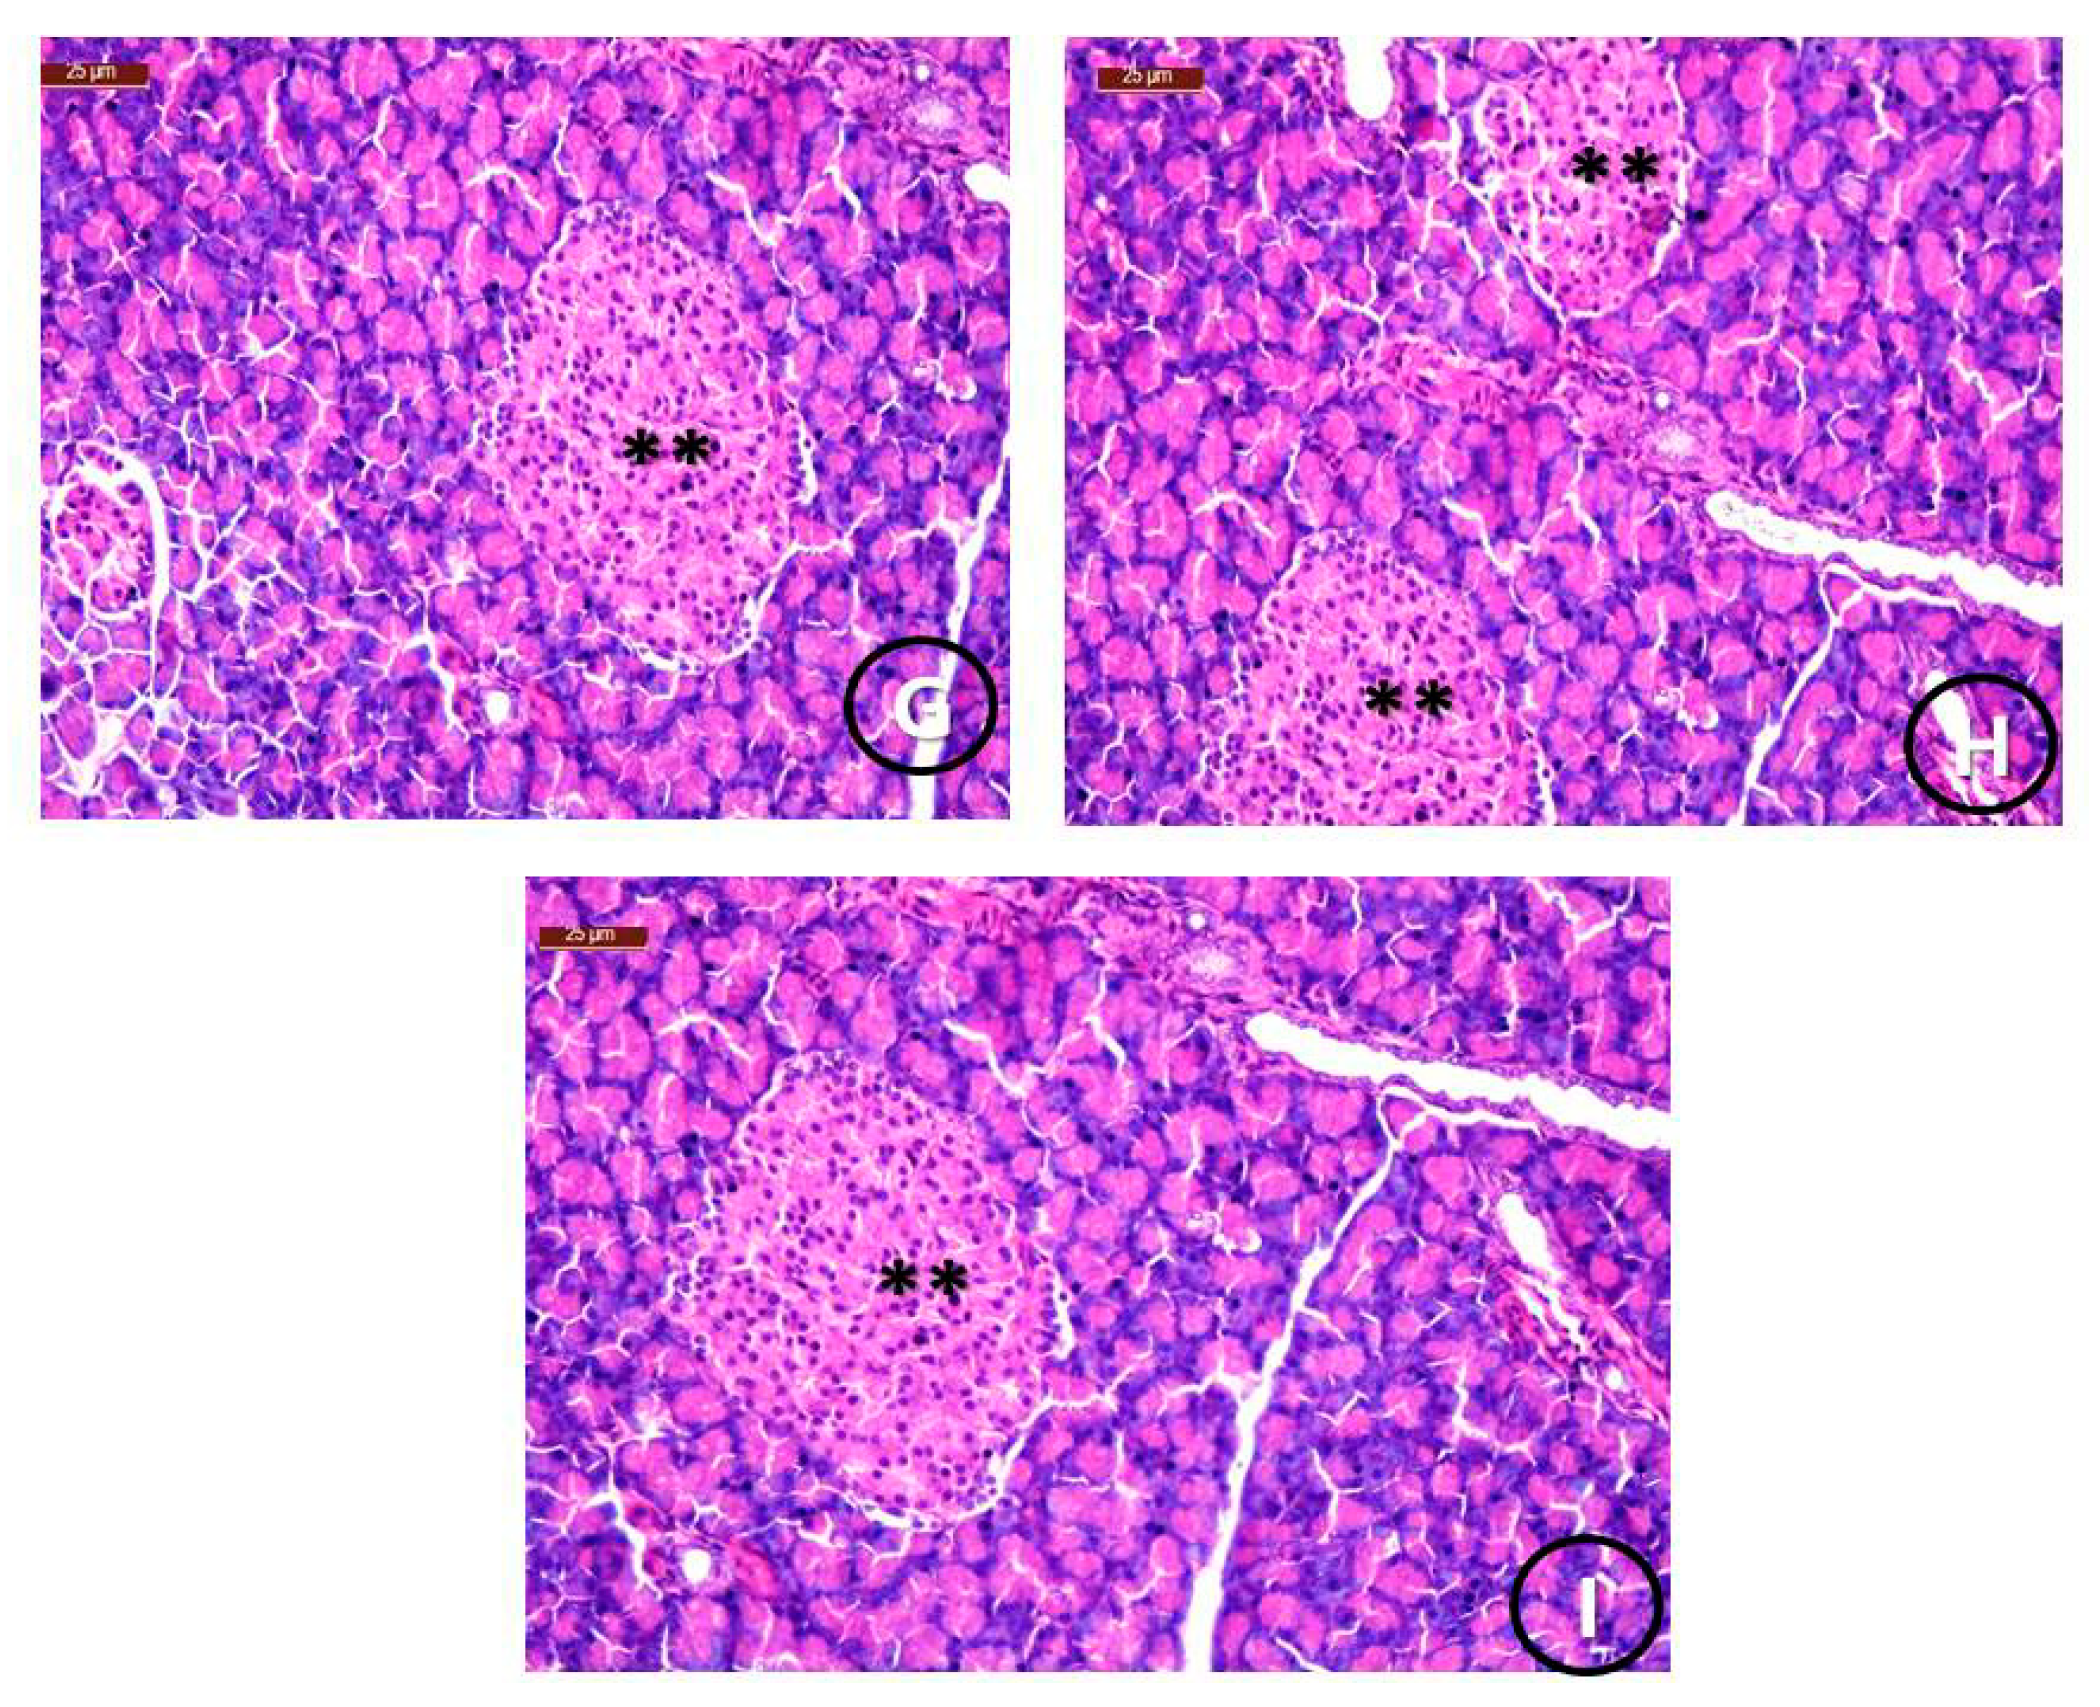

| Groups | Pancreatic Parenchyma | Islets of Langerhans Size | ||||

|---|---|---|---|---|---|---|

| Normal | Detached | Normal | Reduced | Mild | Enlarged | |

| Group 1 (Control) | 90% | 0% | 90% | 0% | 0% | 0% |

| Group 2 (STZ) | 0% | 90% | 0% | 90% | 25% | 0% |

| Group 3 (STZ +STG) | 80% | 25% | 80% | 0% | 80% | 80% |

| Group 4 (STZ+ STG/Cu) | 90% | 0% | 90% | 0% | 25% | 90% |

| Group 5 (STZ+ STG/Mg) | 90% | 0% | 90% | 0% | 25% | 90% |

| Group 6 (STZ+ STG/Zn) | 90% | 0% | 90% | 0% | 25% | 90% |

| Group 7 (STZ+ STG/Ca) | 90% | 0% | 90% | 0% | 25% | 90% |

| Group 8 (STZ+ STG/Cr) | 90% | 0% | 90% | 0% | 25% | 90% |

| Group 9 (STZ+ STG/Se) | 90% | 0% | 90% | 0% | 25% | 90% |